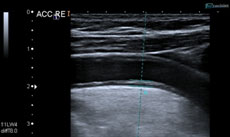

Nicht hörbare Ultraschallwellen (im Bereich von 1-15 Mega-Hertz) werden vom Gewebe des Körpers verschieden stark reflektiert, so dass ein Computer hieraus nahezu in Echtzeit ein Bild in Graustufen errechnen kann (B-Bild-Sonographie). Zudem werden Schallwellen durch fließendes Blut je nach Geschwindigkeit des Blutflusses mit veränderter Frequenz reflektiert (Doppler-Sonographie). Mit der Kombination dieser Methoden (Farbduplex-Sonographie) können Gefäßwandveränderungen und Änderungen des Blutflusses zuverlässig und gefahrlos dargestellt werden.

Gefäßveränderungen sind für jeden dritten Schlaganfall verantwortlich und werden mittels Doppler- und Farbduplexsonographie am Hals und im Schädel selbst mit hoher Treffsicherheit erfasst.

Die genaue und frühzeitige Diagnose mittels Ultraschall dient der optimalen Schlaganfallvorsorge und der rechtzeitigen Klärung von Behandlungsmöglichkeiten.

Sonographie – Frühmarker der Arteriosklerose

Noch bevor es zu Verengungen der Halsschlagadern kommt, können schon beginnende Gefäßwandverdickungen bei früher Arteriosklerose sonographisch erfasst werden (sog. „Intima-Media-Dicke“= Dicke der inneren und mittleren Gefäßwandschichten). Dies dient dazu Gefäß-Risikofaktoren besonders gut zu suchen und optimal zu behandeln. Im Idealfall können sich solche frühe Arteriosklerosezeichen dann sogar zurückbilden.